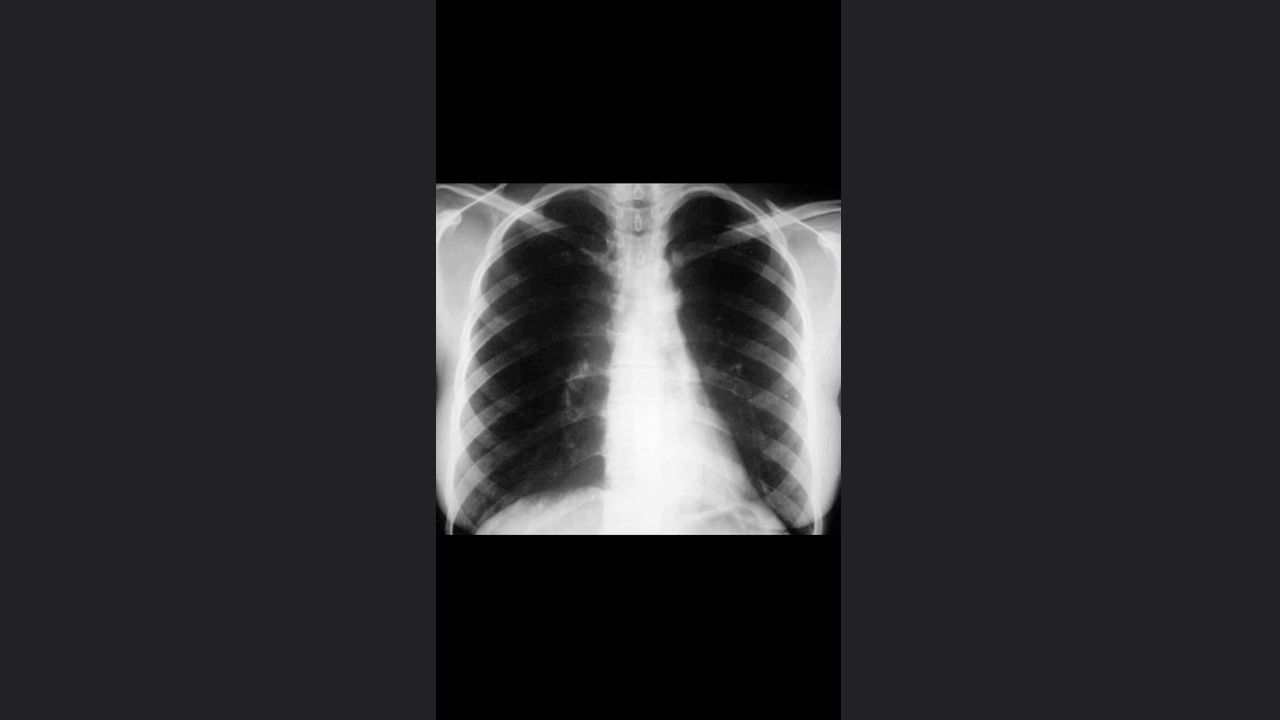

Pulmón en lesión alveolar

Características del EPOC

Sindrome de condensación pulmonar